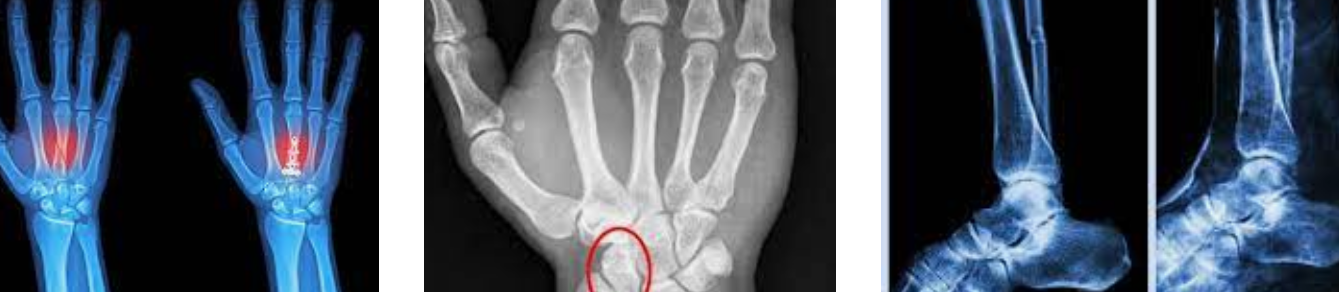

일단 가장 기본적으로는 누르면 아픕니다. 약간 멍이 들어을 때 누르면 아픈 것처럼 그 강도가 더 심합니다. 그리고 찌릿함이 계속 나타나게 됩니다. 그리고 심한 경우는 퉁퉁 부어오르기도 합니다. 하지만 실금이기에 실제로 엑스레이로 잘 안 나오는 경우도 있습니다.